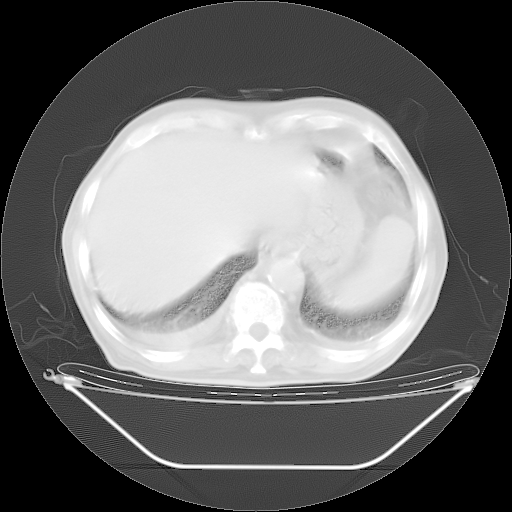

胸腹部CT,诊断意见:左上肺叶钙化灶、左侧胸膜局限性增厚并钙化、胆囊炎。描述部分肺组织呈磨玻璃样改变。

今天复查肺部CT,发现双肺广泛磨玻璃样改变。所以我把3月19日和5月9日相隔50天的肺部CT上传。请大家会诊。

5月9日肺部CT(在4月27日齐鲁医院肺部CT描述部分肺组织磨玻璃样改变,12天后肺组织广泛磨玻璃样改变)